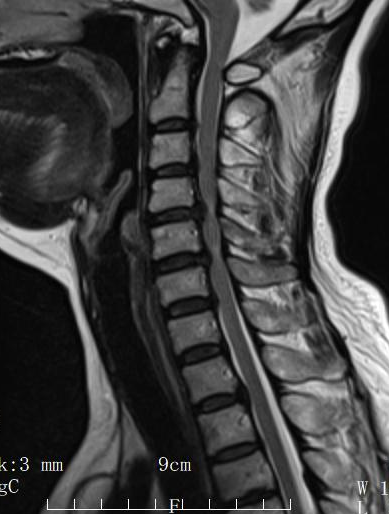

影像學(xué)檢查顯示,患者頸椎管容積嚴(yán)重縮小,猶如一段被嚴(yán)重?cái)D壓的“隧道”,內(nèi)部的脊髓神經(jīng)長(zhǎng)期受壓,已出現(xiàn)不可逆的損傷變性信號(hào)。這是導(dǎo)致患者一系列嚴(yán)重癥狀的根本原因。

術(shù)前MRI